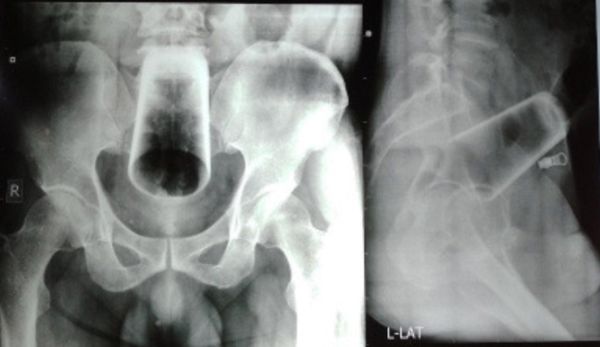

尼泊尔一名47岁的已婚男子因连续3天便秘而就医,随后向医生坦承,是自己喝醉酒后将一个12公分的玻璃酒杯塞入肛门内,结果却拿不出来。医生照X光确认位置后,无法徒手拔出又怕把杯子弄破,最后只好安排男子开刀将杯子取出。

医生先透过X光扫描发现,这个12公分长的玻璃杯卡在直肠和结肠的上部,且医生也判断,无法直接伸手从直肠内取出,因为怕无法抓住杯子,也担心玻璃杯会在过程中破裂,导致肠道受伤。最后只能开刀将结肠割开,才顺利将杯子取出。